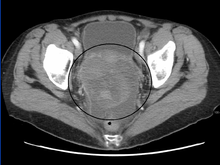

A very large ovarian cancer as seen on CT

Diagnosis of ovarian cancer starts with a physical examination (including a pelvic examination), a blood test (for CA-125 and sometimes other markers), and transvaginal ultrasound.[14] Sometimes a rectovaginal examination is used to help plan a surgery.[18] The diagnosis must be confirmed with surgery to inspect the abdominal cavity, take biopsies (tissue samples for microscopic analysis), and look for cancer cells in the abdominal fluid. This helps to determine if an ovarian mass is benign or malignant.[14]

CT scanning is preferred to assess the extent of the tumor in the abdominopelvic cavity, though magnetic resonance imaging can also be used.[13] CT scanning can also be useful for finding omental caking or differentiating fluid from solid tumor in the abdomen, especially in low malignant potential tumors. However, it may not detect smaller tumors. Sometimes, a chest x-ray is used to detect metastases in the chest or pleural effusion. Another test for metastatic disease, though it is infrequently used, is a barium enema, which can show if the rectosigmoid colon is involved in the disease. Positron emission tomography, bone scans, and paracentesis are of limited use; in fact, paracentesis can cause metastases to form at the needle insertion site and may not provide useful results.[18] However, paracentesis can be used in cases where there is no pelvic mass and ascites is still present.[18] A physician suspecting ovarian cancer may also perform mammography or an endometrial biopsy (in the case of abnormal bleeding) to assess the possibility of breast malignancies and endometrial malignancy, respectively. Vaginal ultrasonography is often the first-line imaging study performed when an adnexal mass is found. Several characteristics of an adnexal mass indicate ovarian malignancy; they usually are solid, irregular, multilocular, and/or large; and they typically have papillary features, central vessels, and/or irregular internal septations.[16] However, SCST has no definitive characteristics on radiographic study.[20]